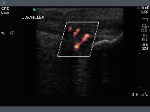

Achilles Tendon: Power Doppler communication with retrocalcaneal bursa